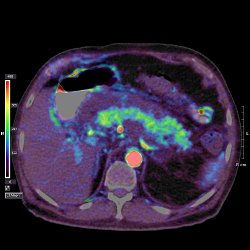

CT